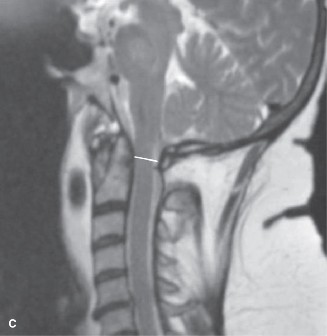

The correct answer is (A). The patient has a history that is consistent with cervical spondylotic myelopathy (CSM). Plain films confirm the presence of spondylosis. His history and examination indicates spinal cord dysfunction. The next study that should be ordered is an MRI of the cervical spine. A CT would be a reasonable alternative if the patient had a contraindication for MRI. That being said, a CT myelogram would be preferred. An EMG is not likely to be positive or useful in the diagnosis of myelopathy. A lumbar puncture is also not likely to be useful in making the diagnosis as there are usually no associated hallmark changes of the cerebrospinal fluid (CSF) in a patient with myelopathy. Advanced images of the patient’s cervical spine (Fig. 1–24) are reviewed. Of the following, which surgical treatment is most appropriate? 1. Laminectomy C3–6

Figure 1–24

The correct answer is (D). The sagittal T2-weighted MRI demonstrates a relatively lordotic spine with multilevel degeneration and cord compression at C3–4, C4–5, and C5–6. There is both anterior and posterior effacement of the CSF. Anterior or posterior procedures might be appropriate. Of note, a posterior procedure, such as laminectomy and fusion or laminoplasty is a reasonable option because of the preserved lordosis. In fact, it has been suggested that either procedure can be performed in a cervical spine with no more than 13 degrees of kyphosis. Effective posterior decompression relies on directly removing the posterior compressive structures (i.e., infolded ligamentum flavum, facet joints) and indirect decompression from the anterior structures (i.e., discs, vertebral body osteophytes) via the spinal cord drifting posteriorly. In this specific case, of the choices, laminectomy and fusion of C2–6 would decompress the stenotic segments. A laminectomy of C3–6 might achieve adequate decompression, but it is not recommended to perform a laminectomy alone as it may result in post-laminectomy kyphosis. An anterior cervical discetomy and fusion (ACDF) might be appropriate, but choice B does not include the most stenotic level, C3–4. Likewise, a corpectomy can be appropriate, but choice C does not include the most stenotic level.